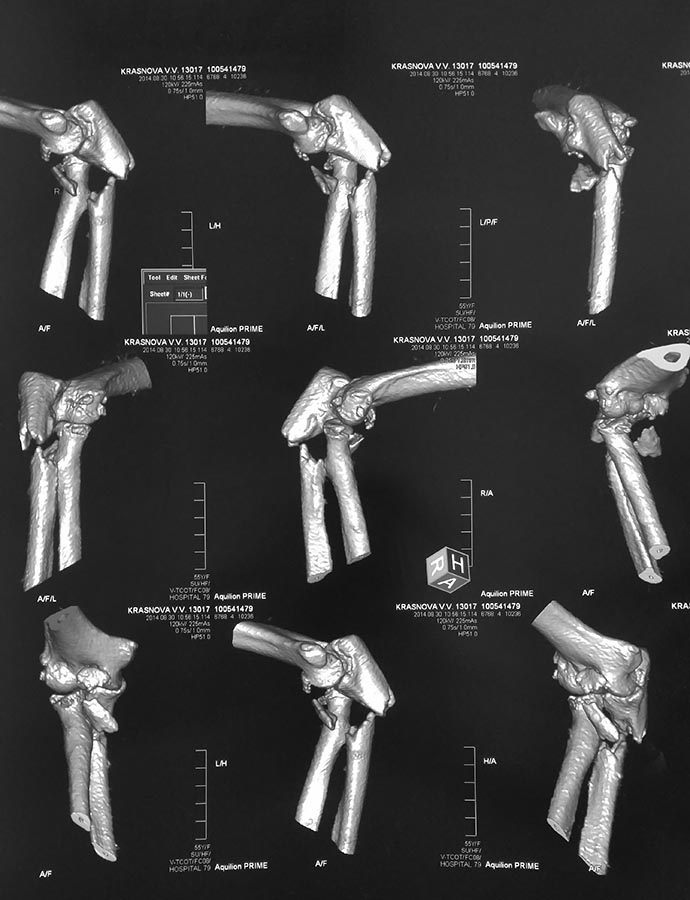

Пациентка 55 лет поступила с оскольчатым переломом локтевой кости в верхней трети, переломом венечного отростка, внутрисуставным переломом головки лучевой кости с вывихом предплечья кзади. При поступлении вывих вправлен. Подскажите тактику оперативного лечения

Это так называемое повреждение Монтеджи II типа (заднее). Необходим остеосинтез локтевой кости пластиной с обязательной фиксацией венечного отростка. Венечный фиксируется первым с помощью шва типа лассо, но окончательная фиксация проводится после остеосинтеза локтевой кости (затягивается петля), также необходим дебридмент головки лучевой кости, но будьте готовы к ее эндопротезированию. Выполнение этих условий позволит избежать релюксации в послеоперационном периоде. Иммобилизация обязательна в ортезе в течение 6 недель, движения разрешены через 7-10 дней при условии стабильности локтевого сустава.

Я советую головку лучевой кости по возможности сохранять или выполнять ее протезирование. Головка луча является важнейшим вторичным стабилизатором локтевого сустава не только против вальгусных нагрузок, но и нагрузок действующих в передне-заднем направлении.Более внимательно изучив КТ видно, что в большей степени сломана ее передняя часть, поэтому, скорее всего, утрачено ее функциональное предназначение ( вопрос об эндопротезировании).

Но ключом является венечный отросток. Если будет нестабильная или неадекватная фиксация этого мелкого фрагмента, вы получите функционально нестабильный сустав. Вот тут большое значение будет иметь воссоздание анатомии головки луча. Если после этого сустав все еще нестабилен, производят шов связок при их повреждении. Если и после этого нестабилен, то необходим шарнирный АНФ на 6 недель. И выскажу мое личное мнение: в локтевом суставе стабильность имеет приоритет над подвижностью. Для жизни достаточно 100 градусов амплитуды сгибания-разгибания - доказано профессором B. F. Morrey. А возраст...как возраст, не столь важно.

Прошу прощения за брюзжание, но все бросились планировать лечение, основываясь по 3D картинкам. Вы у себя в отделениях тоже так делаете: прячете Rg-граммы и КТ-срезы подальше, рассматриваете мультяшные картинки, в большинстве случаев подходящие для родственников больного, так как рентгенограммы они не разумеют?

Уважаемый Артур Саакян, покажите, пожалуйста Rg-граммы и КТ- срезы, по которым можно анализировать повреждение головки лучевой кости и венечного отростка.